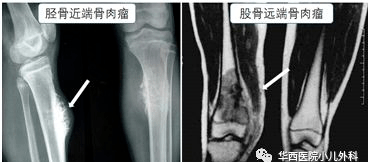

骨癌的专业名称为恶性骨肿瘤,其中骨肉瘤是最常见的原发性恶性骨肿瘤,约占所有恶性骨肿瘤的1/3,主要发生在青少年,多发生在10-25岁,发病率主要位于股骨远端、胫骨近端和肱骨近端。主要表现为疼痛和肿胀。

在医院,为了在早期诊断和发现恶性疾病,如骨癌,医生将根据儿童的临床表现结合辅助检查如x光、核磁共振和血液进行进一步分析,并通过定期随访等多种手段判断哪条腿疼痛。